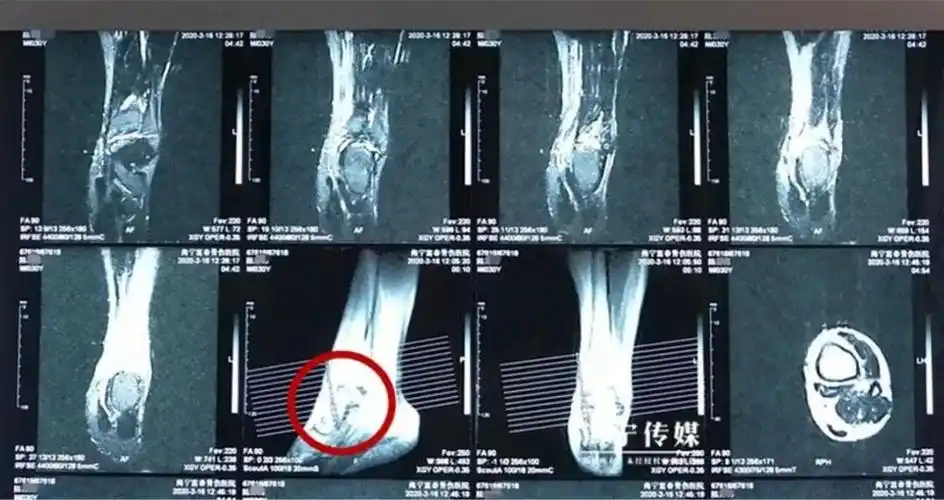

【科普】男子崴了脚不当回事,半年后,可怕的一幕出现了